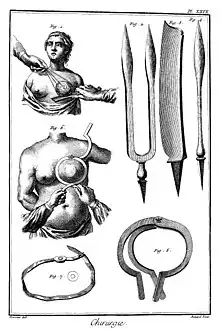

History

Because of its visibility, breast cancer was the form of cancer most often described in ancient documents.[224]: 9–13 Because autopsies were rare, cancers of the internal organs were essentially invisible to ancient medicine. Breast cancer, however, could be felt through the skin, and in its advanced state often developed into fungating lesions: the tumour would become necrotic (die from the inside, causing the tumour to appear to break up) and ulcerate through the skin, weeping fetid, dark fluid.[224]: 9–13

The oldest discovered evidence of breast cancer is from Egypt and dates back 4200 years, to the Sixth Dynasty.[225] The study of a woman's remains from the necropolis of Qubbet el-Hawa showed the typical destructive damage due to metastatic spread.[225] The Edwin Smith Papyrus describes eight cases of tumours or ulcers of the breast that were treated by cauterization. The writing says about the disease, "There is no treatment."[226] For centuries, physicians described similar cases in their practices, with the same conclusion. Ancient medicine, from the time of the Greeks through the 17th century, was based on humoralism, and thus believed that breast cancer was generally caused by imbalances in the fundamental fluids that controlled the body, especially an excess of black bile.[224]: 32 Alternatively it was seen as divine punishment.[227]

Mastectomy for breast cancer was performed at least as early as AD 548, when it was proposed by the court physician Aetios of Amida to Theodora.[224]: 9–13 It was not until doctors achieved greater understanding of the circulatory system in the 17th century that they could link breast cancer's spread to the lymph nodes in the armpit. In the early 18th century the French surgeon Jean Louis Petit performed total mastectomies that included removing the axillary lymph nodes, as he recognized that this reduced recurrence.[228] Petit's work built on the methods of the surgeon Bernard Peyrilhe, who in the 17th century additionally removed the pectoral muscle underlying the breast, as he judged that this greatly improved the prognosis.[229] But poor results and the considerable risk to the patient meant that physicians did not share the opinion of surgeons such as Nicolaes Tulp, who in the 17th century proclaimed "the sole remedy is a timely operation". The eminent surgeon Richard Wiseman documented in the mid 17th century that following 12 mastectomies, two patients died during the operation, eight patients died shortly after the operation from progressive cancer and only two of the 12 patients were cured.[230]: 6 Physicians were conservative in the treatment they prescribed in the early stages of breast cancer. Patients were treated with a mixture of detox purges, blood letting and traditional remedies that were supposed to lower acidity, such as the alkaline arsenic.[231]: 24

When in 1664 Anne of Austria was diagnosed with breast cancer, the initial treatment involved compresses saturated with hemlock juice. When the lumps increased the King's physician commenced a treatment with arsenic ointments.[231]: 25 The royal patient died 1666 in atrocious pain.[231]: 26 Each failing treatment for breast cancer led to the search for new treatments, spurring a market in remedies that were advertised and sold by quacks, herbalists, chemists and apothecaries.[232] The lack of anesthesia and antiseptics made mastectomy a painful and dangerous ordeal.[230] In the 18th century, a wide variety of anatomical discoveries were accompanied by new theories about the cause and growth of breast cancer. The investigative surgeon John Hunter claimed that neural fluid generated breast cancer. Other surgeons proposed that milk within the mammary ducts led to cancerous growths. Theories about trauma to the breast as cause for malignant changes in breast tissue were advanced. The discovery of breast lumps and swellings fueled controversies about hard tumours and whether lumps were benign stages of cancer. Medical opinion about necessary immediate treatment varied.[230]: 5 The surgeon Benjamin Bell advocated removal of the entire breast, even when only a portion was affected.[233]

Breast cancer was uncommon until the 19th century, when improvements in sanitation and control of deadly infectious diseases resulted in dramatic increases in lifespan. Previously, most women had died too young to have developed breast cancer.[234] In 1878, an article in Scientific American described historical treatment by pressure intended to induce local ischemia in cases when surgical removal were not possible.[235] William Stewart Halsted started performing radical mastectomies in 1882, helped greatly by advances in general surgical technology, such as aseptic technique and anesthesia. The Halsted radical mastectomy often involved removing both breasts, associated lymph nodes, and the underlying chest muscles. This often led to long-term pain and disability, but was seen as necessary to prevent the cancer from recurring.[224]: 102–106 Before the advent of the Halsted radical mastectomy, 20-year survival rates were only 10%; Halsted's surgery raised that rate to 50%.[224]: 1

Breast cancer staging systems were developed in the 1920s and 1930s to determining the extent to which a cancer has developed by growing and spreading.[224]: 102–106 The first case-controlled study on breast cancer epidemiology was done by Janet Lane-Claypon, who published a comparative study in 1926 of 500 breast cancer cases and 500 controls of the same background and lifestyle for the British Ministry of Health.[236] Radical mastectomies remained the standard of care in the USA until the 1970s, but in Europe, breast-sparing procedures, often followed by radiation therapy, were generally adopted in the 1950s.[224]: 102–106 In 1955 George Crile Jr. published Cancer and Common Sense arguing that cancer patients needed to understand available treatment options. Crile became a close friend of the environmentalist Rachel Carson, who had undergone a Halsted radical mastectomy in 1960 to treat her malign breast cancer.[237]: 39–40 The US oncologist Jerome Urban promoted superradical mastectomies, taking even more tissue, until 1963, when the ten-year survival rates proved equal to the less-damaging radical mastectomy.[224]: 102–106 Carson died in 1964 and Crile went on to published a wide variety of articles, both in the popular press and in medical journals, challenging the widespread used of the Halsted radical mastectomy. In 1973 Crile published What Women Should Know About the Breast Cancer Controversy. When in 1974 Betty Ford was diagnosed with breast cancer, the options for treating breast cancer were openly discussed in the press.[237]: 58 During the 1970s, a new understanding of metastasis led to perceiving cancer as a systemic illness as well as a localized one, and more sparing procedures were developed that proved equally effective.[238]